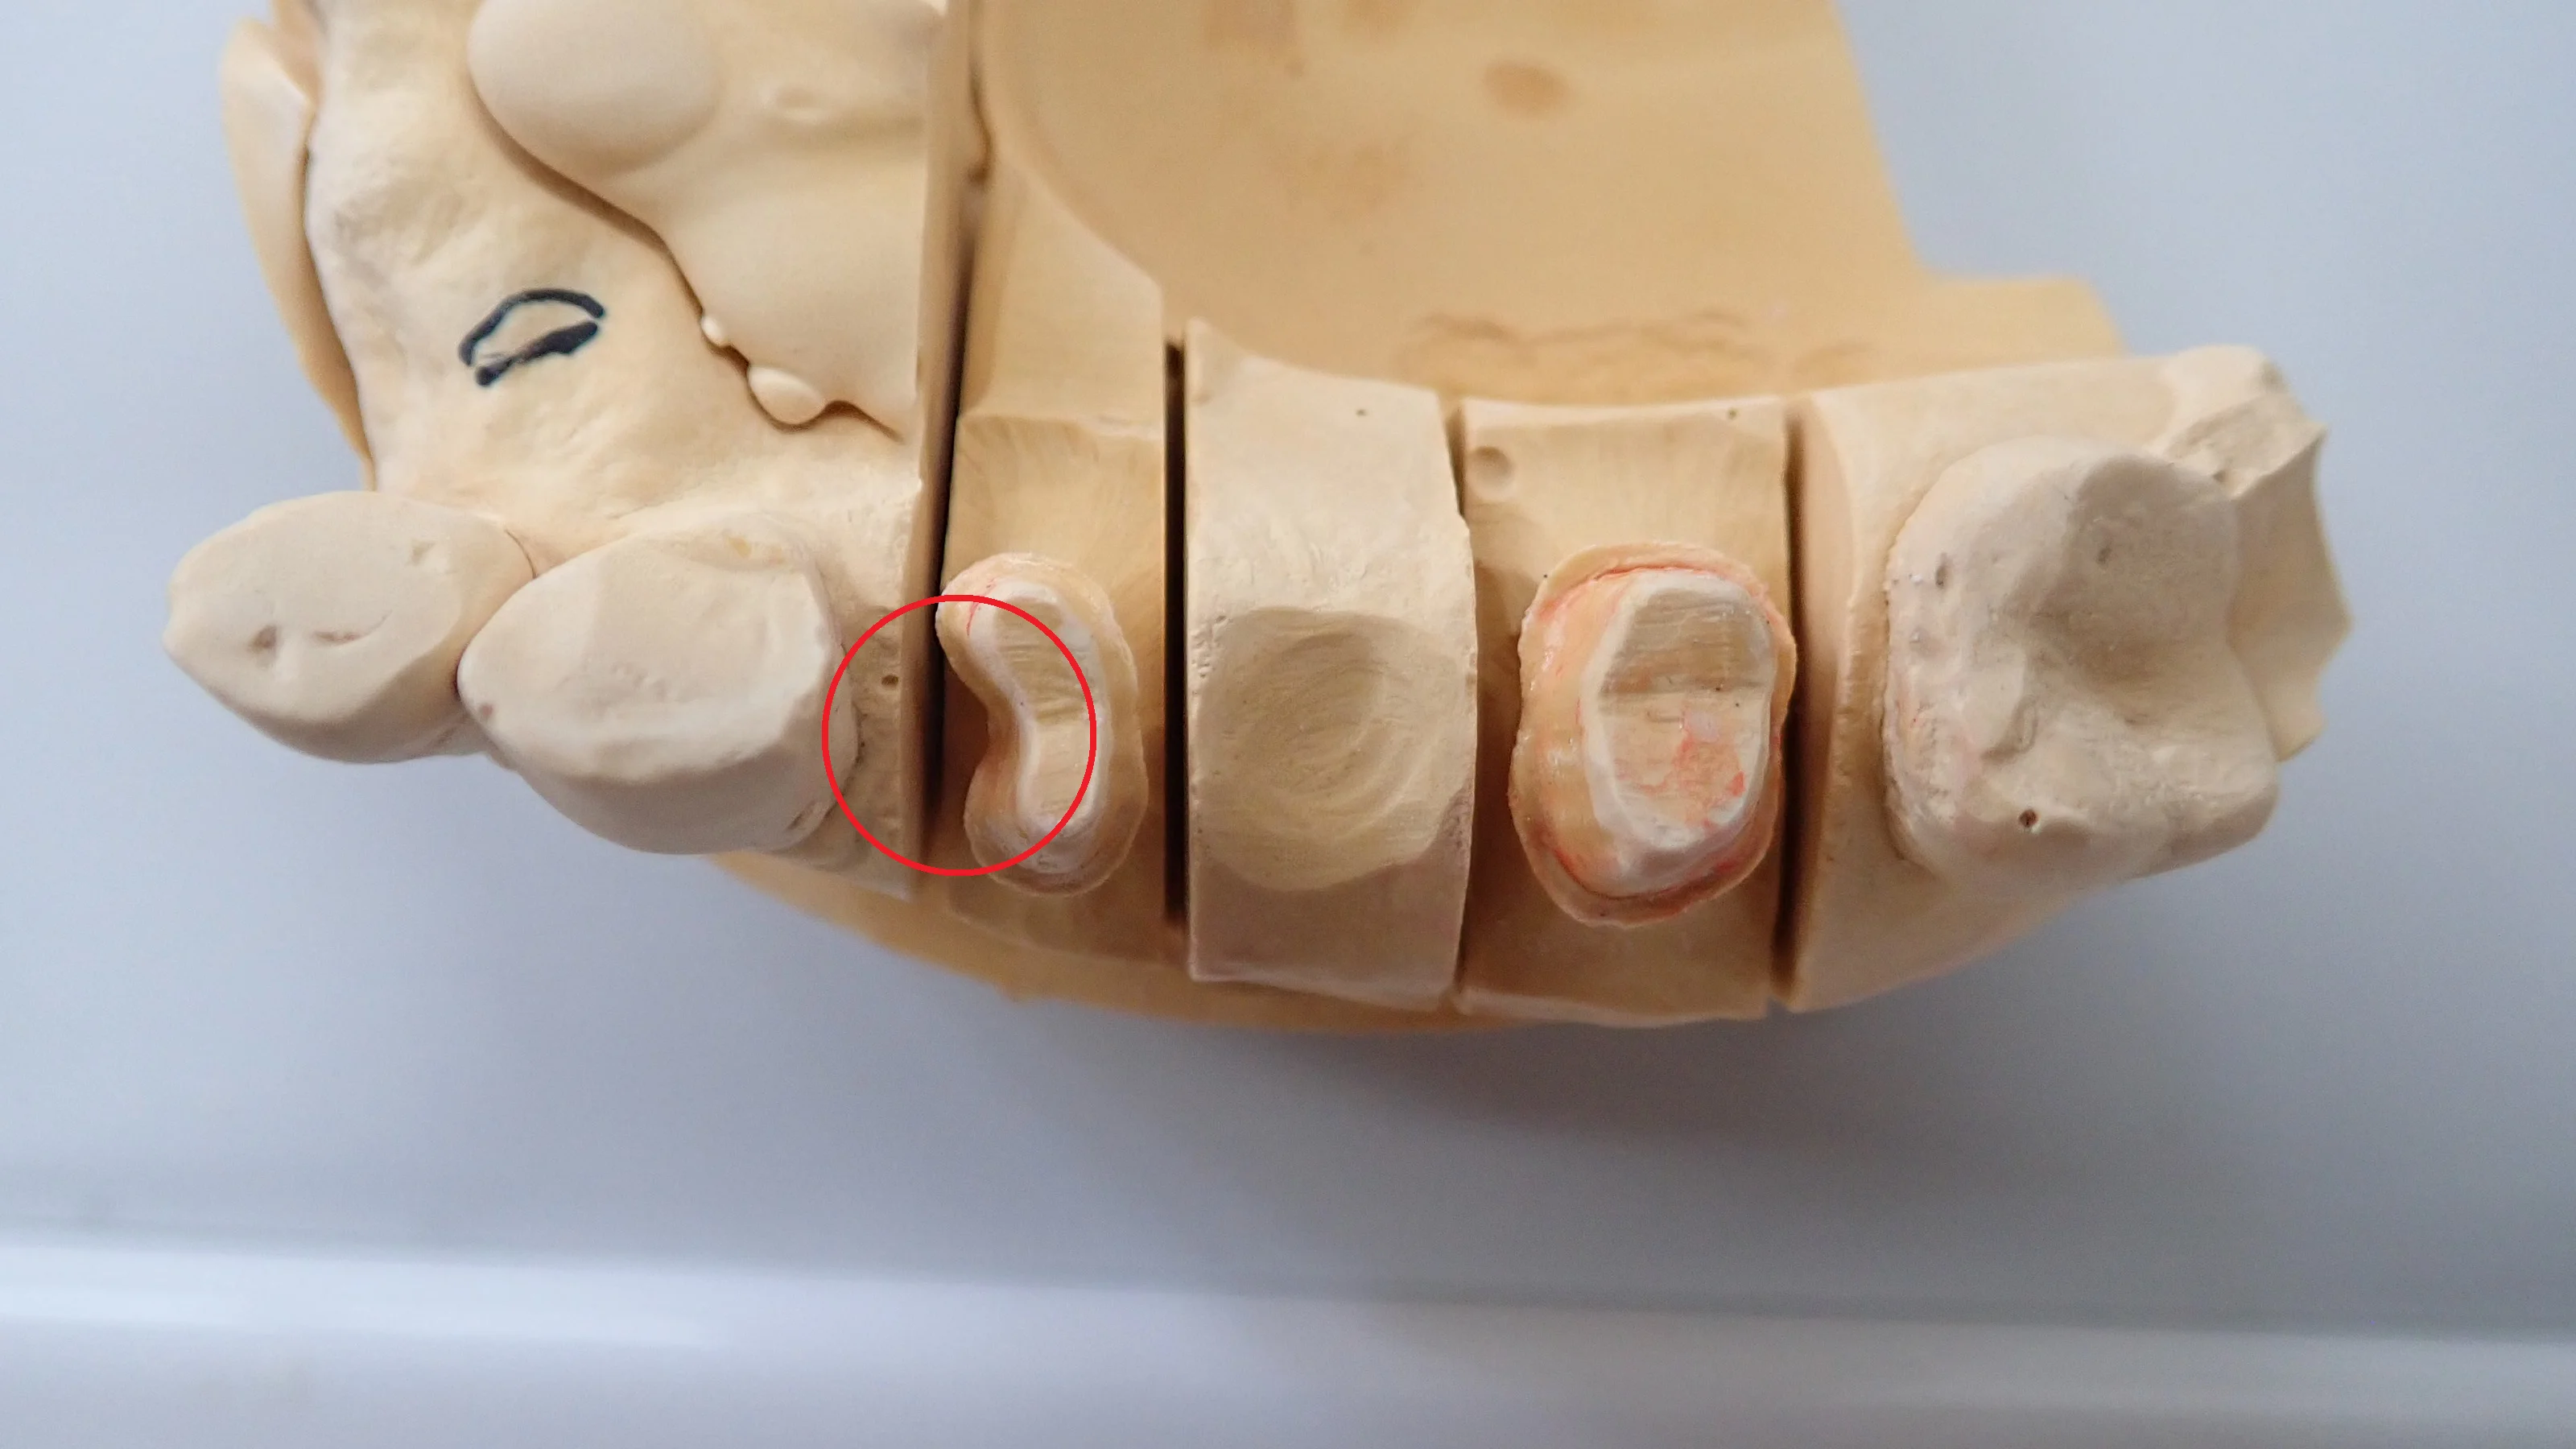

【歯科医師向け】窩洞形成時のエナメル質マイクロクラックを防ぐ:接着修復の成功率向上のために

エナメル質に生じる「マイクロクラック」は、肉眼では見えないほど小さな亀裂ですが、接着修復のマージン適合や長期予後に影響する可能性があります。 本記事では、窩洞形成時にマイクロクラックが生じる主な原因(バーの粒度・切削条件・窩洞設計・歯質やブ…

続きを読む →